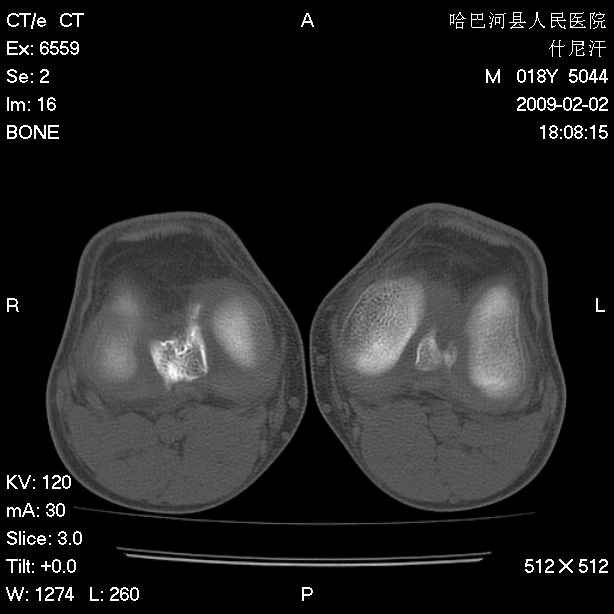

标题: CT17889:外伤后右膝关节反复疼痛3年余 [打印本页]

标题: CT17889:外伤后右膝关节反复疼痛3年余

ct未见明显异常。关节腔未见明显积液,半月板未见明显撕裂。但最好还是mri看看韧带及半月板情况。